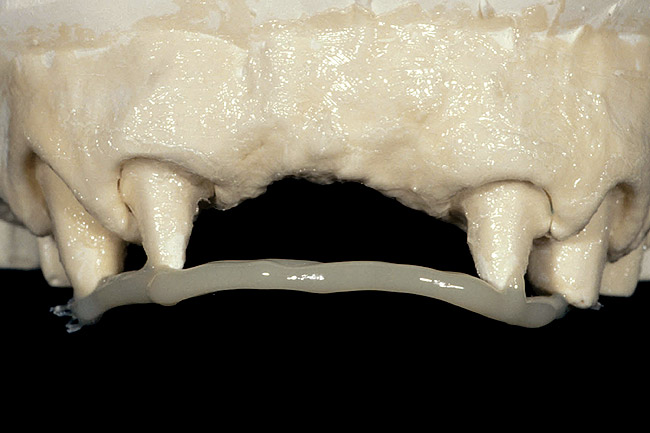

I typically reinforce only when pontics are present, and generally only when there are two or more pontics and the temporary must last more than 1 to 2 months.18 I use fiber for reinforcement, and I prefer to make the reinforced temporary indirectly on a model, starting with a wax-up and clear matrix prior to preparing the teeth.

To reinforce temporary restorations, begin by preparing the teeth and making an impression of the preparations. Pour the impression with one-third die stone and two-thirds mounting stone, so it sets quickly. Then ensure that the matrix fits the model. The fiber can now be placed across the preparations on the model and tacked into place with flowable composite. Once the fiber is positioned, try the matrix back on to verify clearance between the fiber and the matrix. If the clearance is acceptable, remove the matrix and reinforce the fiber by adding more flowable composite across its length. Finally, lubricate all areas of the model with petroleum jelly or foil substitute, keeping all lubricant off the fiber. Then, load the matrix with the desired temporary material and seat it over the preparations and the fiber. After curing, it can be trimmed and seated in the patient’s mouth (Figure 17, Figure 18, Figure 19, Figure 20 and Figure 21).

Figure 18  Fiber reinforcement is tacked to the preparations with flowable composite and reinforced, after which the model is fabricated.

Figure 18